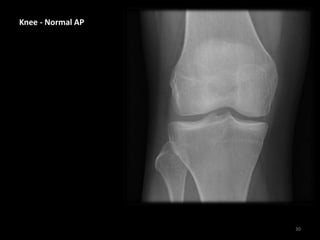

Knee - Normal AP

The patella is often not

clearly seen on this view

Knee – Normal AP

• This x-ray showing the

cartilage ( hyaline ) ,

meniscus and joint soft

tissue.

• We can not specific any

abnormality for knee

components unless we

request MRI for the

patient.